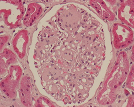

Histopatologia

Observação Macro e Microscópica de material biológico retirado por:

- Biópsias(pequenas amostras resultantes de endoscopias digestivas, colonoscopias, broncoscopias, transplantes ou de pequenas cirurgias, por exemplo retalhos de pele);

- Peças cirúrgicas(resultantes da ressecção de órgãos como vesicula biliar, útero, estómago, próstata, tumores);

- Exames Intraoperatórios(também chamados Exames Extemporâneos efectuados durante os actos operatórios para orientação e/ou decisão cirúrgica).

Histoquímica

Técnica que, através de reações químicas, permite evidenciar determinados constituintes celulares, depósitos exógenos e microorganismos.